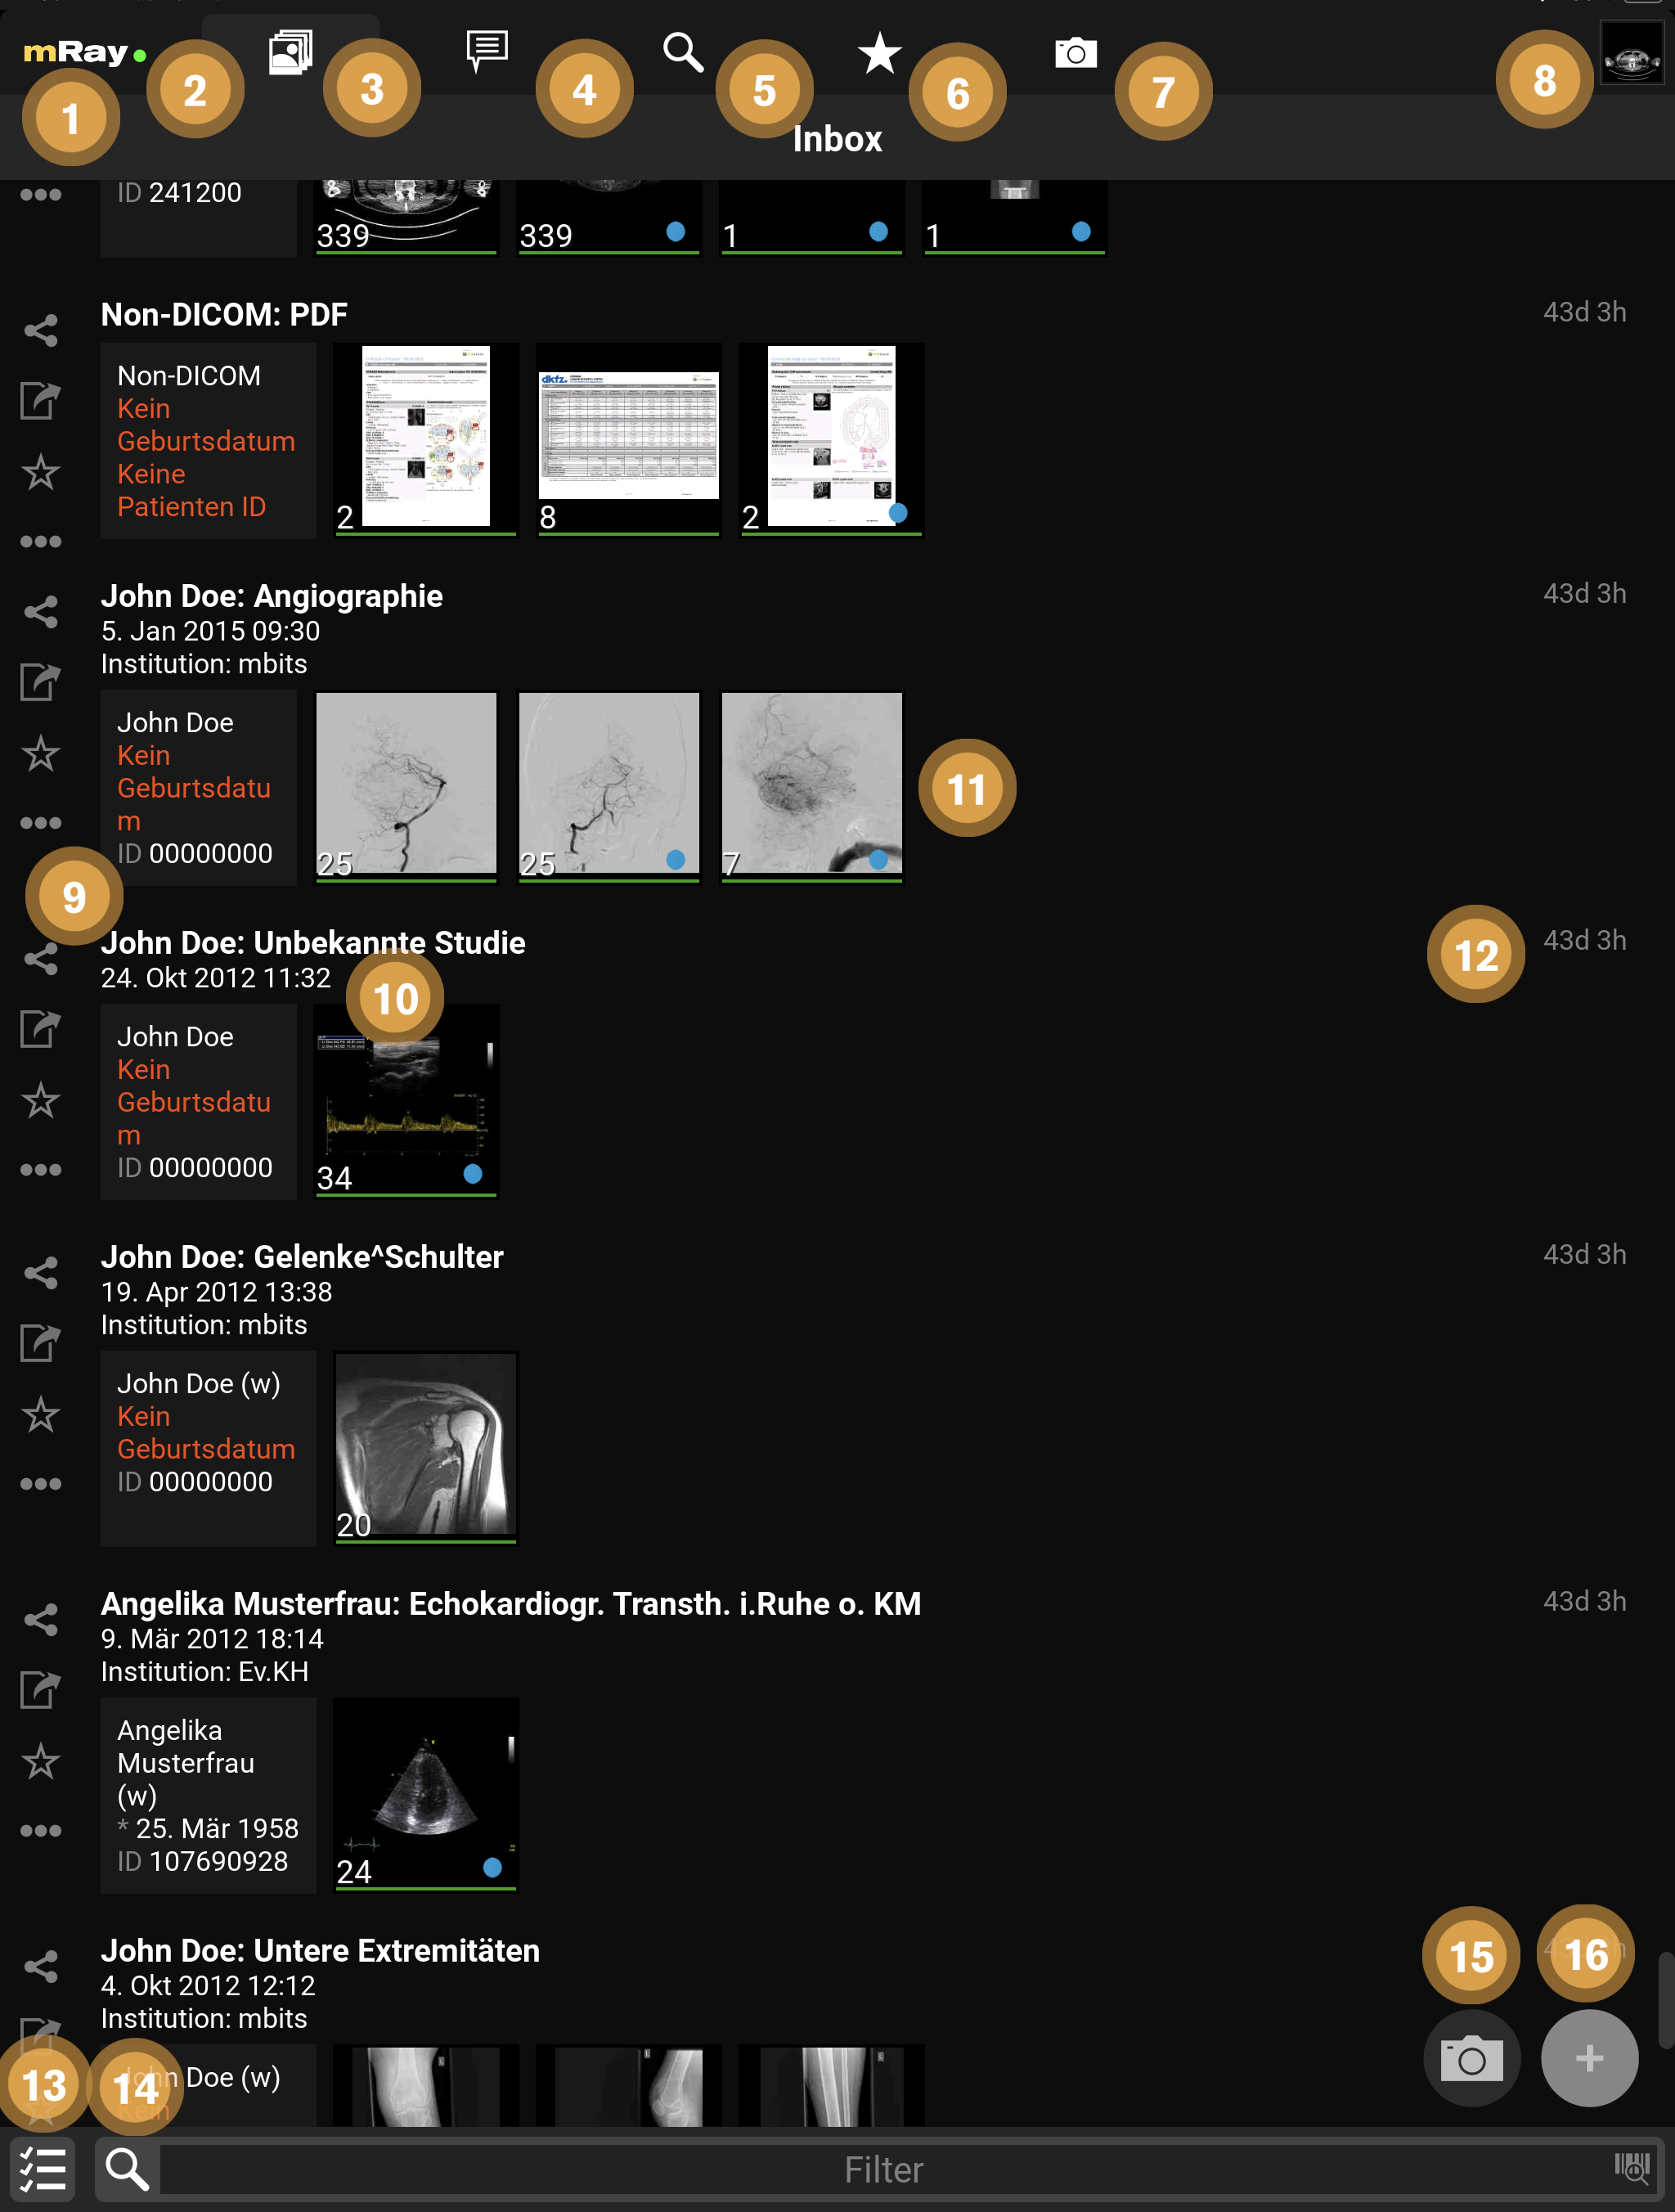

9.1. Inbox

Nach dem Einloggen öffnet sich die „Inbox“ (Inbox). Über diese können Sie den gewünschten DICOM Datensatz selektieren, der Ihnen über den eingestellten Server zur Verfügung gestellt wurde. Sie sehen hier also alle am mRay-Server vorliegenden Daten, auf die Sie Zugriffsrechte haben.

|

Scrollen durch längere Listen

Scrollen Sie durch Listen, indem Sie nach oben/unten wischen oder nutzen Sie die Scrollleiste an der rechten Seite einer Liste, um schnell durch diese zu navigieren. |

-

Durch Anklicken des mRay-Logos öffnet sich das Hauptmenü (siehe Hauptmenü).

-

Ein grünes Symbol zeigt an, dass Sie mit dem Server verbunden sind. Bei einem roten Symbol können Sie mit den lokal gespeicherten Daten arbeiten, aber erhalten natürlich keine neuen Datensätze.

-

Wechseln zur Inbox oder zum Anfang der Liste, wenn dies der aktive Reiter ist.

-

Wechseln zum Messaging (nur vorhanden, falls diese Funktion in Ihrem System aktiviert wurde)

-

Wechseln zur Suche. Hier können Sie den gesamten für Sie verfügbaren Datenbestand durchsuchen. Sie haben außerdem die Möglichkeit Suchanfragen an ein PACS zu stellen (falls eingerichtet).

-

Wechseln zu den Favoriten: Favoriten können Sie mit Hilfe der Stern-Symbole (Punkt 8) markieren. Favoriten funktionieren als eine Art "Lesezeichen" und werden vom automatischen Speichermanagement der Anwendung als Letztes gelöscht (d. h. nur wenn das Löschen notwendig ist aufgrund der Einstellungen zur Datenvorhaltung oder aufgrund eines niedrigen Speicherplatzes auf dem Gerät).

-

Wechseln zur Fotodokumentation

-

Klicken Sie hier, um zur Bildansicht (Viewer) mit den zuvor geöffneten Bildern zurückzukehren.

-

Hier können Sie schnell und einfach ganze Studien teilen

, als Favorit markieren

, als Favorit markieren  bzw. auf ihr Gerät exportieren

bzw. auf ihr Gerät exportieren  .

Weitere Aktionen für die ganze Studie lassen sich über das Kontextmenü

.

Weitere Aktionen für die ganze Studie lassen sich über das Kontextmenü  ausführen.

ausführen. -

Hier werden Informationen bzw. auch fehlende Informationen und Metadaten zum Patient angezeigt.

-

Hier sehen Sie eine Übersicht der Serien innerhalb der Studie. Durch Anklicken einer Studie kommen Sie in die Serienauswahl (siehe Serienauswahl). Der grüne Balken unter jedem Vorschaubild zeigt an ob der Datensatz lokal auf Ihr Gerät heruntergeladen und offline verfügbar ist.

-

Hier erscheint, wann der Datensatz in der Inbox ankam (d. h. durch Schicken aus dem PACS bzw. Suche im Datenbestand). mRay kann so konfiguriert werden, dass Datensätze automatisch nach 'X' Stunden wieder vom Gerät gelöscht werden (Standard: Nach 8 Stunden).

-

Hier können mehrere Studien zum Teilen ausgewählt werden.

-

Hier können Sie die Inbox nach einer Texteingabe filtern. Bitte beachten: Hiermit starten Sie keine PACS-Suchanfrage! Bitte benutzen Sie dazu Punkt 3 Suche. Beachten Sie auch die Hinweise zu Sonderzeichen im Kapitel „Bekannte Probleme“.

-

Fotofunktion aufrufen: Siehe Abschnitt Fotodokumentation zur näheren Erläuterung.

-

Datei-Upload: Laden Sie eigene DICOM Daten auf Ihren Server. Nur verfügbar wenn vom Server unterstützt.